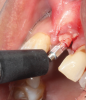

(15.) The primary stability of the implant was assessed using RFA.

Figure 15

(16.) Because the implant’s ISQ value was above 65, immediate provisionalization could be performed with relative confidence.

Figure 16